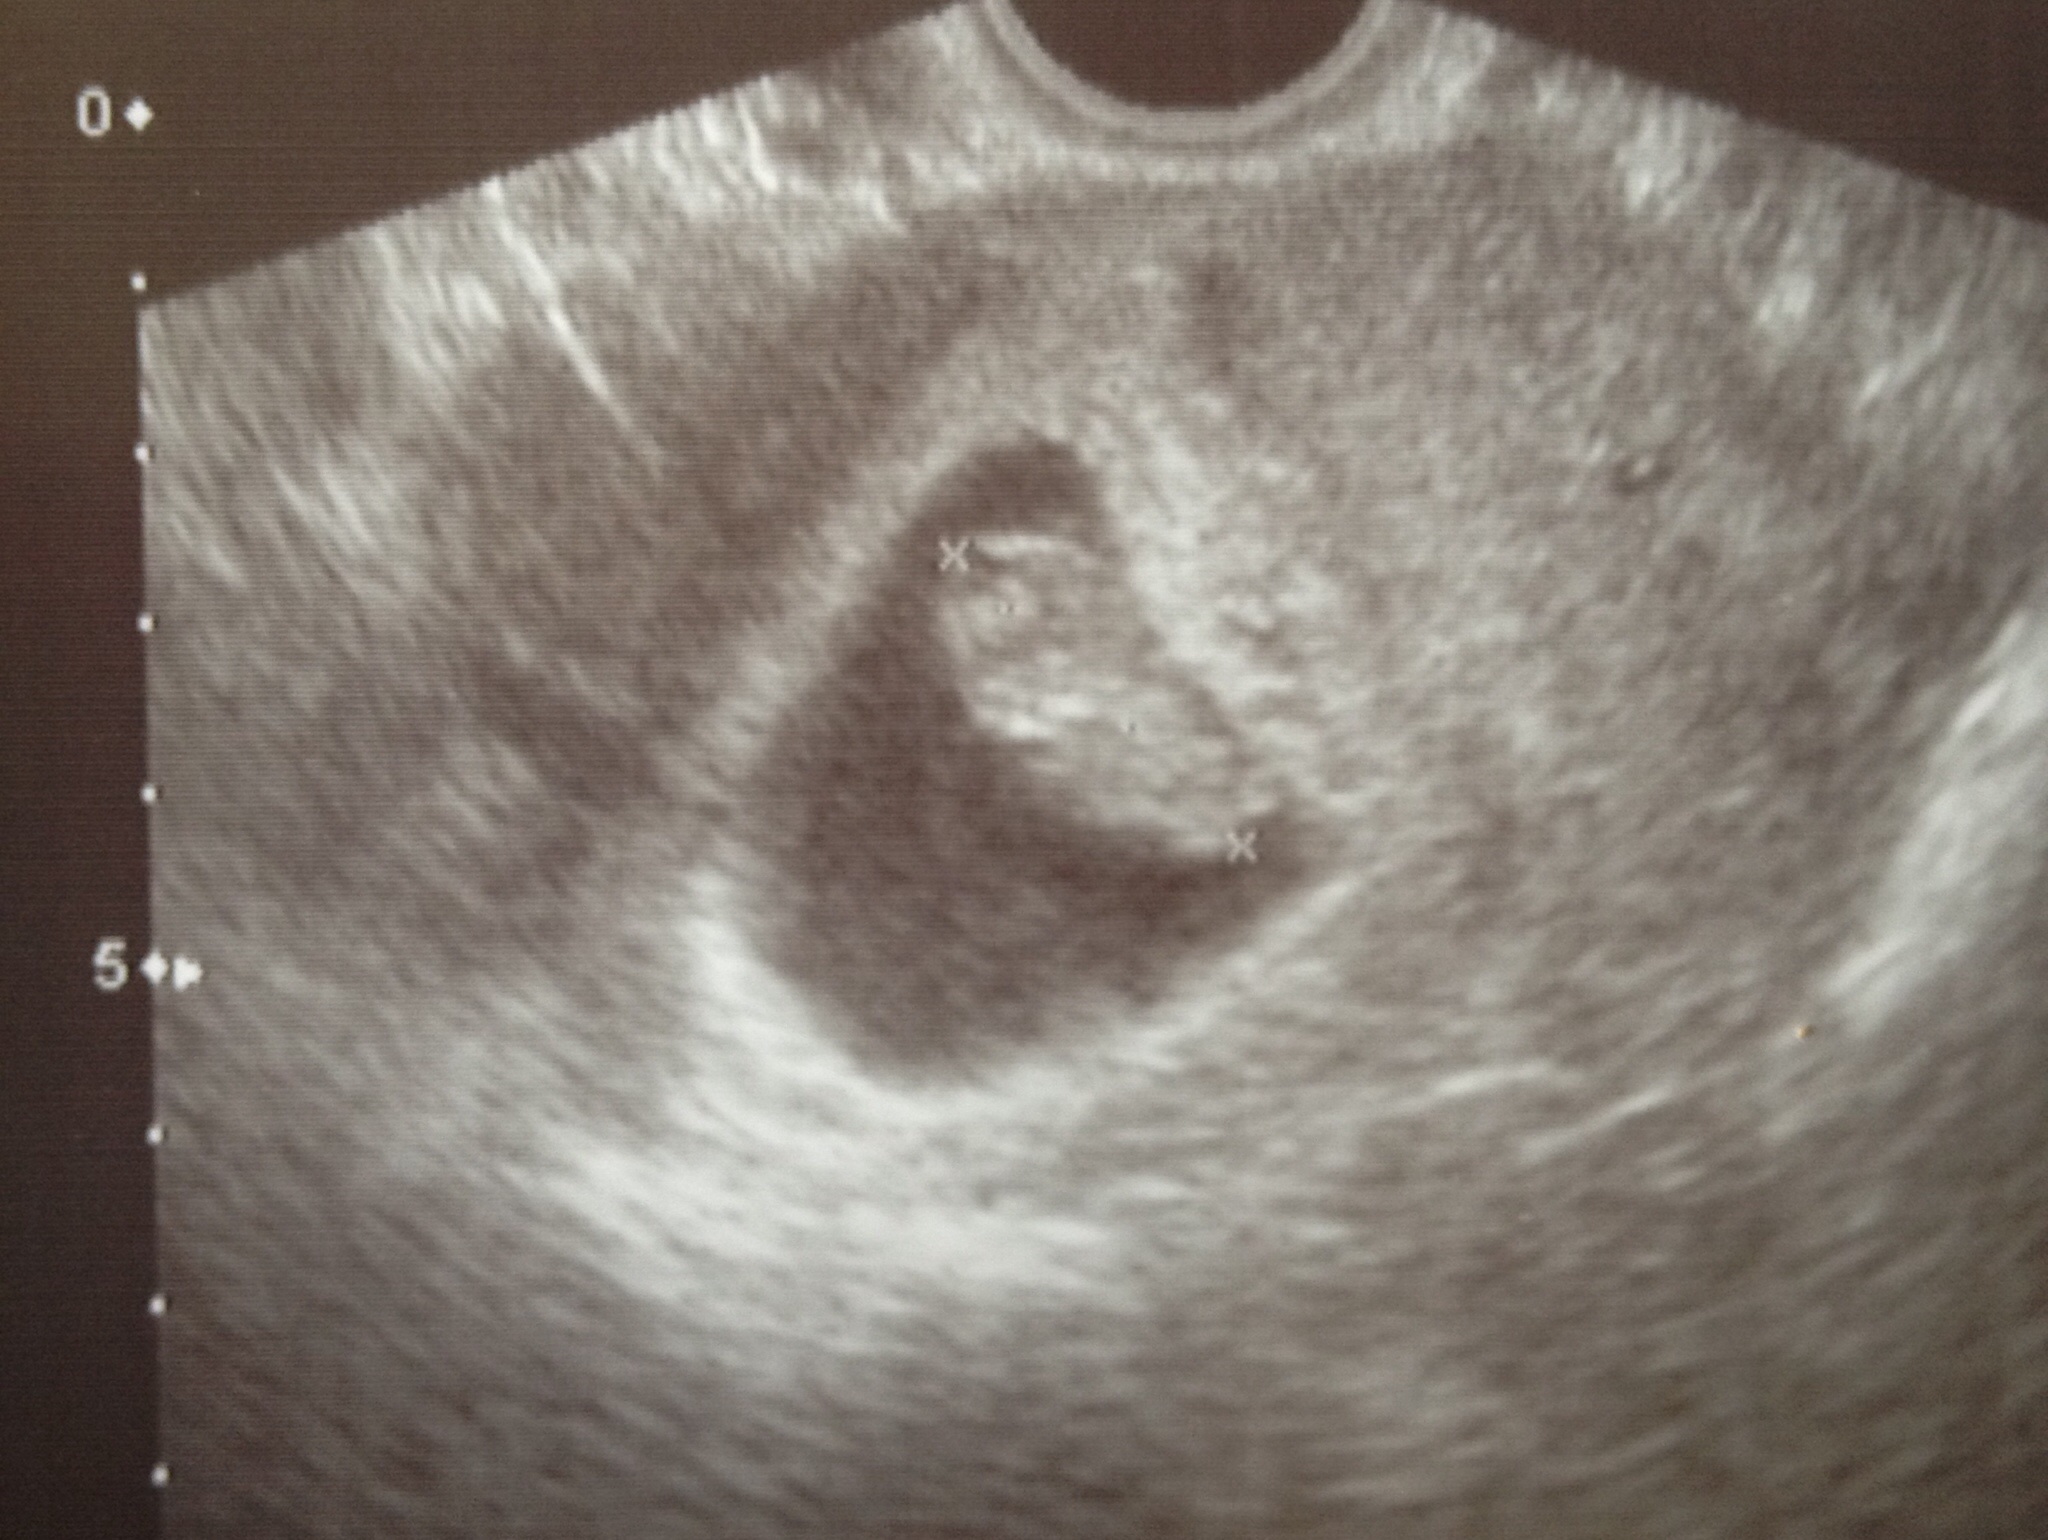

We had our first ultrasound today (7wks5days) ... Seems we had no reason to be nervous! We could see the little heart beating and I measured at 7wks3days everything appears to be just as it should be. RELIEF!

We had our first sono today & it was great! Measured right on target at 7.1, though the tech had do a trans-vaginal since the reader wasn't finding anything on my tummy. We got to see the little heart flutter- so cute!!